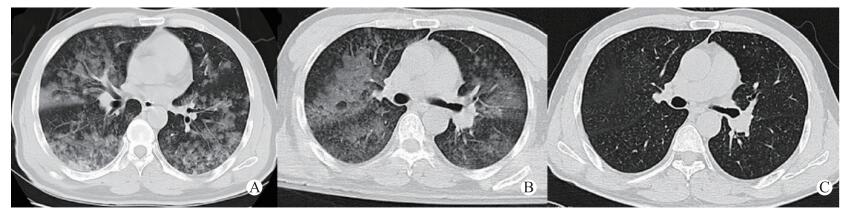

1 资料与方法患者,男,45岁。因“吸入氯气后胸闷气急伴视物模糊9 h”于2017年5月7日晚8时入我院急诊。患者9 h前家务劳动时不慎吸入氯气,当时稍有胸闷气急,伴视物模糊,流泪不止,用大量清水冲洗眼部,未做特殊处理; 后患者胸闷气急症状逐渐加重,伴有咳嗽,无胸痛,来我院急诊就诊。查体:T 37℃,BP 145/89 mmHg(1 mmHg=0.133 kPa),HR 121次/min,RR 28次/min,急诊室测患者未吸氧情况下氧饱和度为70%,神志清,两肺可及少许湿啰音,腹软,无压痛、反跳痛、肌紧张。立即予储氧面罩吸氧后氧饱和度维持在90%~95%左右,急诊血气分析提示, pH 7.37,PO2 68.4 mmHg, PCO2 44.3 mmHg, BE -2.57 mmol/L, SB 22.3 mmol/L。查胸部CT(图 1A)提示,两肺广泛斑片状影; 其余血检查基本正常。初步诊断:1.氯气中毒; 2.急性呼吸窘迫综合征,为进一步治疗收住急诊ICU病房。

| 图 1 患者入院2 h(A)、第3天(B)及第5天(C)胸部CT变化 |

入我科急诊ICU后予继续给予储氧面罩吸氧,氧饱和度仅能维持在90%~92%,RR:35次/min,HR:135次/min; 患者自诉胸闷气急症状不能缓解,呈端坐位呼吸。与家属充分沟通后改为经鼻高流量吸氧治疗:初始吸入氧体积分数70%, 氧流量50 L/min; 同时给予甲强龙80 mg静滴,沐舒坦化痰及雾化吸入等对症治疗,患者氧饱和度逐渐上升至98%~100%,并自诉胸闷气急症状明显缓解,可平卧。使用高流量氧疗1 h后复查血气分析:pH 7.38,PO2 88.4 mmHg,PCO2 23 mmHg, BE-1.36 mmol/L, SB 23.3 mmol/L; 后患者病情逐渐稳定,氧饱和度维持在95%~99%,仍稍有胸闷气急症状,有咳嗽咳痰,痰容易咳出。3 d后复查胸部CT提示(图 1B):两肺斑片影较前吸收,经鼻高流量吸氧治疗模式调整为:吸入氧体积分数40%, 氧流量30 L/min。患者氧饱和度基本维持在96%以上,胸闷气急症状基本消失,仍稍有咳嗽,无咳痰,入监护室5 d后患者病情好转后转入普通病房,改为普通鼻导管吸氧治疗,7 d后再次复查胸部CT提示(图 1C),肺部斑片状影基本吸收,患者无明显不适主诉,予出院并嘱其定期复查胸部CT。